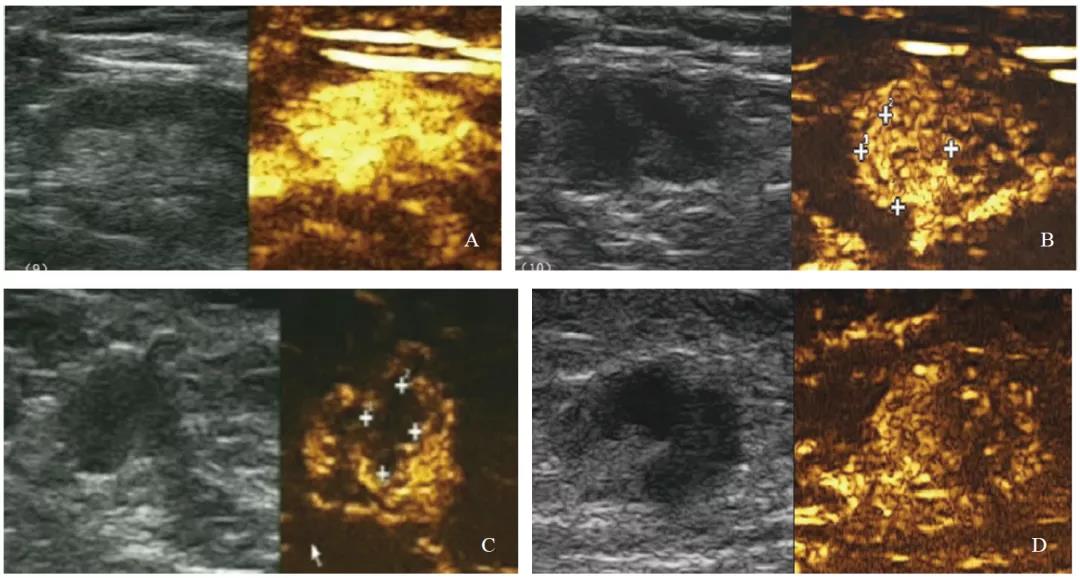

彩色多普勒超声检查发现,非转移性淋巴结多表现为淋巴门型血流(94.62%)。中央型、周围型和混合型血流在转移性淋巴结组百分比为7.69%、2.88%、49.04%,明显高于非转移性淋巴结组0.77%、0.77%及3.85%(P<0.01)。74.04%转移性淋巴结血流丰富,而非转移性淋巴结仅17.69%血流丰富,两组之间差异有统计学意义(P<0.001)。使用血流丰富程度诊断腋窝淋巴结灵敏度、特异度、AUC分别为74.0%、82.3%、0.782。RI≥0.7时特异度最高(98.4%),但灵敏度低(26.0%),AUC为0.622。开始增强时间诊断转移性淋巴结差异无统计学意义(P>0.05)。CEUS检查中,转移性淋巴结多表现为非均匀性增强(P<0.001,图2~3)。

图 3 腋窝淋巴结超声增强模式

A:均匀性增强;B:非均匀性增强,部分性高增强;C:非均匀性增强,部分充盈缺损;D:非均匀性增强,部分性低增强。病理学检查证实A为非转移性淋巴结,B~D为转移性淋巴结。